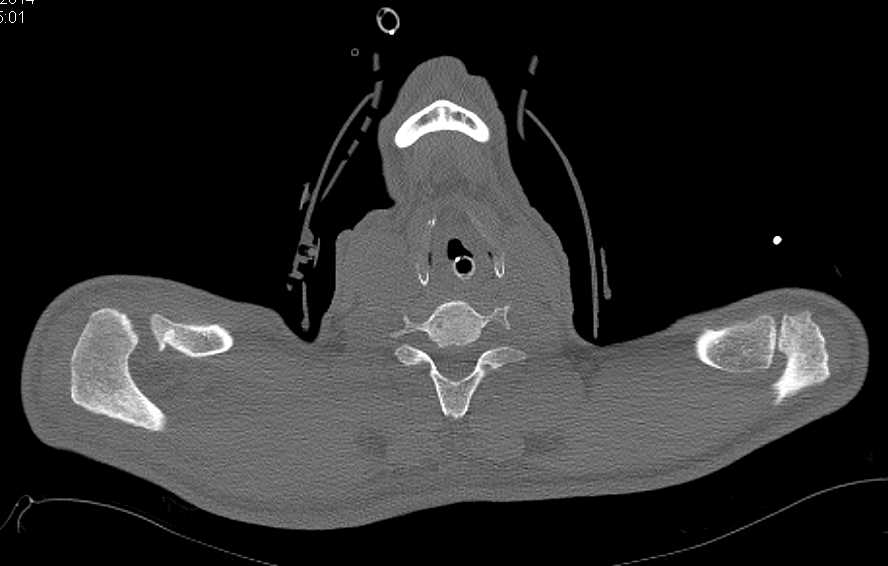

Hematoma in Rectus Muscle